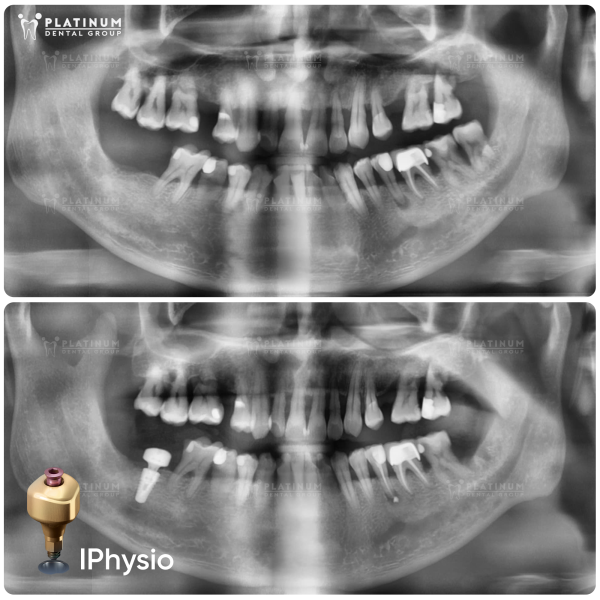

Trước khi thực hiện, bệnh nhân cần được thăm khám kỹ lưỡng, chụp phim CT 3D để đánh giá chính xác tình trạng xương hàm. Dựa trên kết quả này, bác sĩ sẽ lên kế hoạch điều trị phù hợp và xác định có cần phải bổ sung xương hay không.

Khám tổng quát, chụp X-quang và lập kế hoạch cấy ghép Implant

Trước khi bắt đầu quy trình cấy ghép, bác sĩ nha khoa sẽ tiến hành kiểm tra răng miệng tổng quát, chụp phim CT để xác định mật độ và độ dày của xương hàm. Dựa trên kết quả này, bác sĩ sẽ xây dựng phác đồ điều trị phù hợp, bao gồm chi phí và thời gian dự kiến để thực hiện cấy ghép Implant.